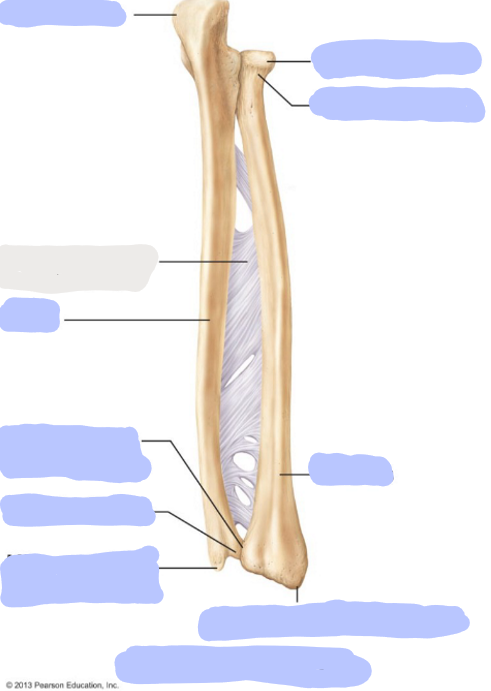

What is this picture of?

Anterior view of the forearm including the Ulna and Radius

What is here?

Where is the Ulna of the Forearm

What is here?

Where is the Radius of the Forearm?

What is here?

Where is the Olecranon of the Ulna?

What is here?

Where is the Coronoid Process of the Ulna?

What is here?

Where is the Trochlear Notch of the Ulna?

What is here?

Where is the Radial Notch of the Ulna?

What is here?

Where is the Head of the Ulna?

What is here?

Where is the Ulnar Styloid Process?

What is here?

Where is the Head of the Radius?

What is here?

Where is the Neck of the Radius?

What is here?

Where is the Radial Styloid Process?

What is here?

Where is the Radial Tuberosity?

What is here?

Where is the Ulnar Notch of the Radius?